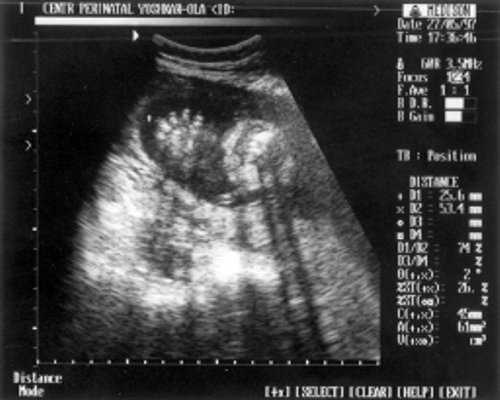

- Кости предплечья = 17,5 мм - 15,5 нед. (рис. 4)

Рис. 4. УЗИ плода - кости предплечья.